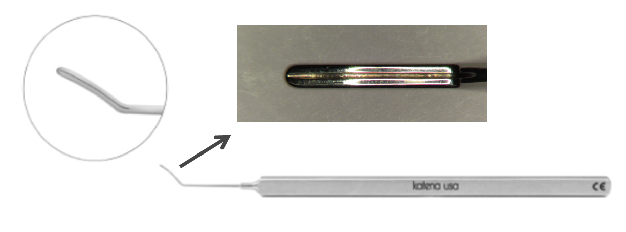

– Ceratoplastia Lamelar Anterior Profunda (DALK)

Segundo o Dr. Gustavo Bonfadini, especialista nesta técnica cirúrgica e desenvolvedor de material cirúrgico para melhorar o resultado desta técnica: “O Transplante Lamelar Anterior Profundo é realizado, preservando-se a camada interior da córnea – chamada de endotélio. Essa técnica é importante, por diminuir a probabilidade de rejeição e melhorar os resultados quando comparada a técnica cirúrgica tradicional.” Retira-se somente o estroma corneano (a parte doente da córnea), mantendo-se a membrana de Descemet e o Endotélio. A técnica conhecida como “Big Bubble”, na qual se separa a membrana de Descemet do estroma utilizando uma bolha de ar é a mais utilizada.

A técnica conhecida como “Big Bubble” (Grande Bolha), é mais difícil de ser realizada, mas representa uma boa opção quando a parte interna da córnea (endotélio) está saudável.

![]()

https://www.katena.com/bonfadini-dalk-spatula-k3-1877